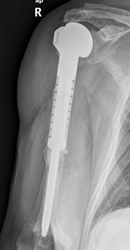

Fig 201 B. Cambios PostQx.

Rx AP. Amputación y colocación de prótesis en el húmero proximal, por resección de osteosarcoma.